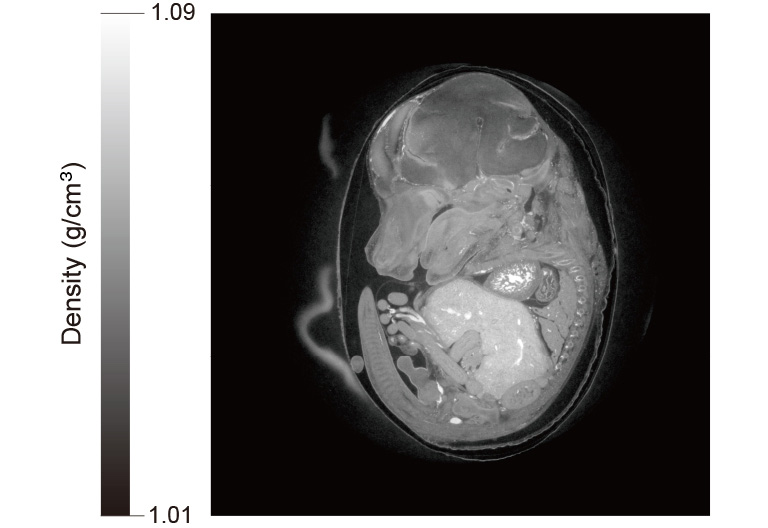

Camera: ORCA-Quest qCMOS camera C15550-20UP

Optics: High-resolution X-ray imaging system (M11427)

Beam line: SPring-8 BL20B2

Exposure time: 15 msec

Total measurement time: 6.5 min

Data courtesy of: SPring-8 BL20B2 beamline by Dr. Masato Hoshino, Senior Scientist in Japan Synchrotron Radiation Research Institute (JASRI)